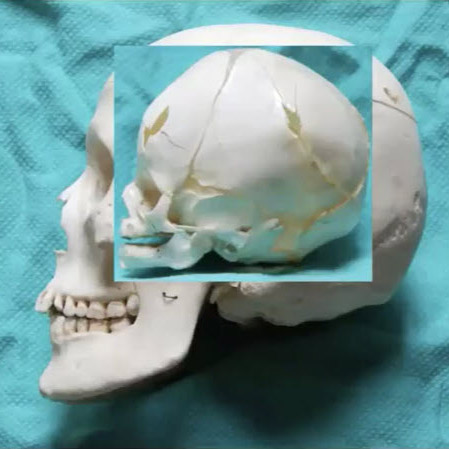

When we look at the pediatric facial skeleton, it's different to the adult skeleton. The pediatric skeleton is primarily cranium, with a small facial volume. It's an 8:1 ratio compared to 2:1 in adults. We’re born without sinuses then start developing them: the maxillary sinus around five to six years of age, and the frontal sinuses again around six to eight. Then, tooth eruption happens around six to eight, which guides vertical growth of our mandible and maxilla. By seven to eight years of age, our cranium and our orbits are about 80% to 90% of the adult size, so an injury at that stage is going to cause less growth disturbance than an injury at six months of age, before things have developed.

The injuries that happen that are low velocity tend to be in the upper face, because these are bigger parts of the face. In terms of the midface, we're talking about the zygomatic arch, the zygoma, maybe the NOE or the nose primarily. They tend to be greenstick injuries. The bones are more cancellous than cortical, so the bone is softer, more "rubbery". The fragments are large and there's less comminution. Again, the displacement is limited, and they tend to be isolated injuries.

Orbital wall fractures are quite unique, pattern-wise, in children compared to adults. We see two separate types of injuries that are less common in adults. The first is an orbital roof fracture, because young children don’t have a frontal sinus which starts developing at age eight.

If the frontal sinus is not present then it can’t act as an airbag, so it doesn’t really protect the brain or the roof of the orbit. The trauma therefore hits the superior orbital rim or frontal bone and causes a fracture along the roof and injury to the central nervous system too. The fragments don’t go into the brain; the brain pushes them down into the orbit. When they’re in the orbit, they cause a reduction of volume. These types of injuries tend to happen in slightly younger children, when the head is a bit smaller compared to the face. They come with CNS injuries and often need to be treated not only by us but together with our neurosurgery colleagues.

Roof fractures are often blow-in type fractures in which the bone fragments push down into the orbit. The patient will present with proptosis—the eye will be down and out—they might have double vision and sometimes significant pressure on their globe, so we often want our ophthalmology colleagues involved as well.